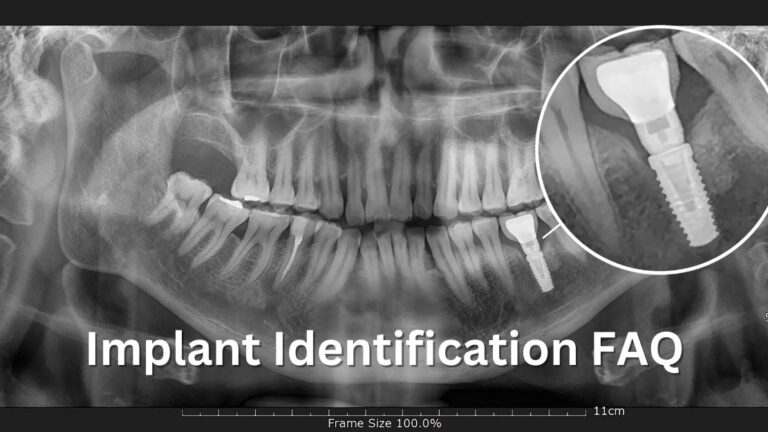

Your Implant identification guide to determine the brand, type, or size of an unknown dental implant before performing an implant mechanical rescue.